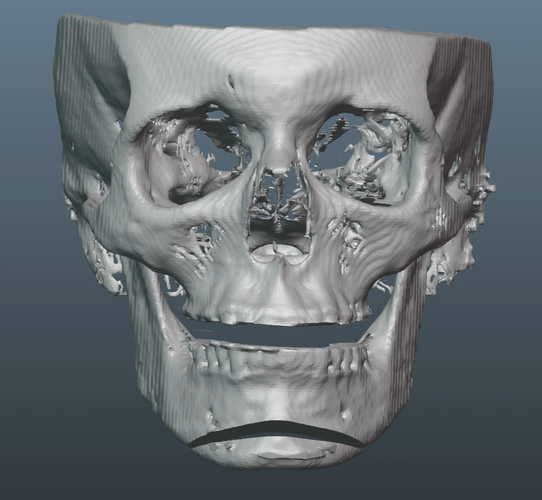

Old silicone wraparound:

-Already has wraparound silicone implant.

-Misplaced badly on left side.

-Implant had unideal curvatures in general, too blocky.

-Patient liked the height of old implants, but requested a slightly wider design.

-Patient also desired more volume around the infras and malars.

Old silicone wraparound: